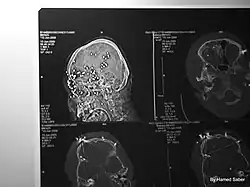

Sepehr Azami (Persian: سپهر اعظمی), was 23 years old at the time of injury. Azami was attending protests in Karaj on 3 November 2022 (40th day ceremony commemorating the death of young protester Hadis Najafi) when he was shot multiple times by pellet guns. More than 80 pellets were discovered inside of his body, causing catastrophic damage, including to one of his eyes. Azami was in a comatose state in hospital for 33 days before succumbing to his injuries in 6 December 2022.[46]